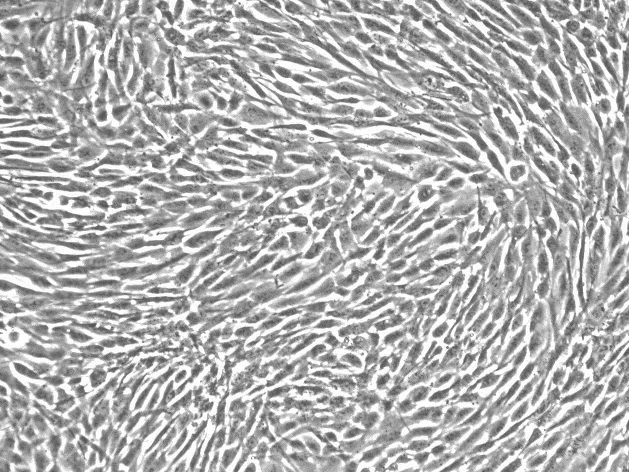

MDA-MB-231

MDA-MB-231人乳腺癌细胞简介:

中文名称:人乳腺癌细胞

简称:MDA-MB-231

形态:上皮细胞样

背景资料:MDA-MB-231来自患有转移乳腺腺癌的51岁女病人的胸水。在裸鼠和ALS处理的BALB/c小鼠中,它能形成低分化腺癌(III级)。